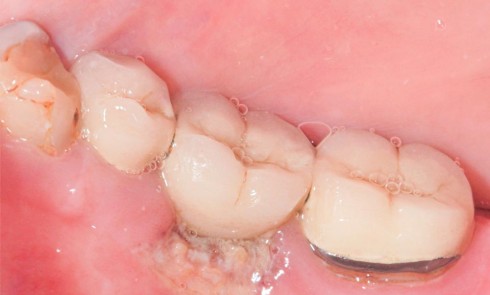

Article réservé à nos abonnés Attention aux herpès récurrents atypiques

Situation clinique Anamnèse. Une patiente âgée de 38 ans a consulté en urgence pour une douleur gingivale et palatine, apparue...